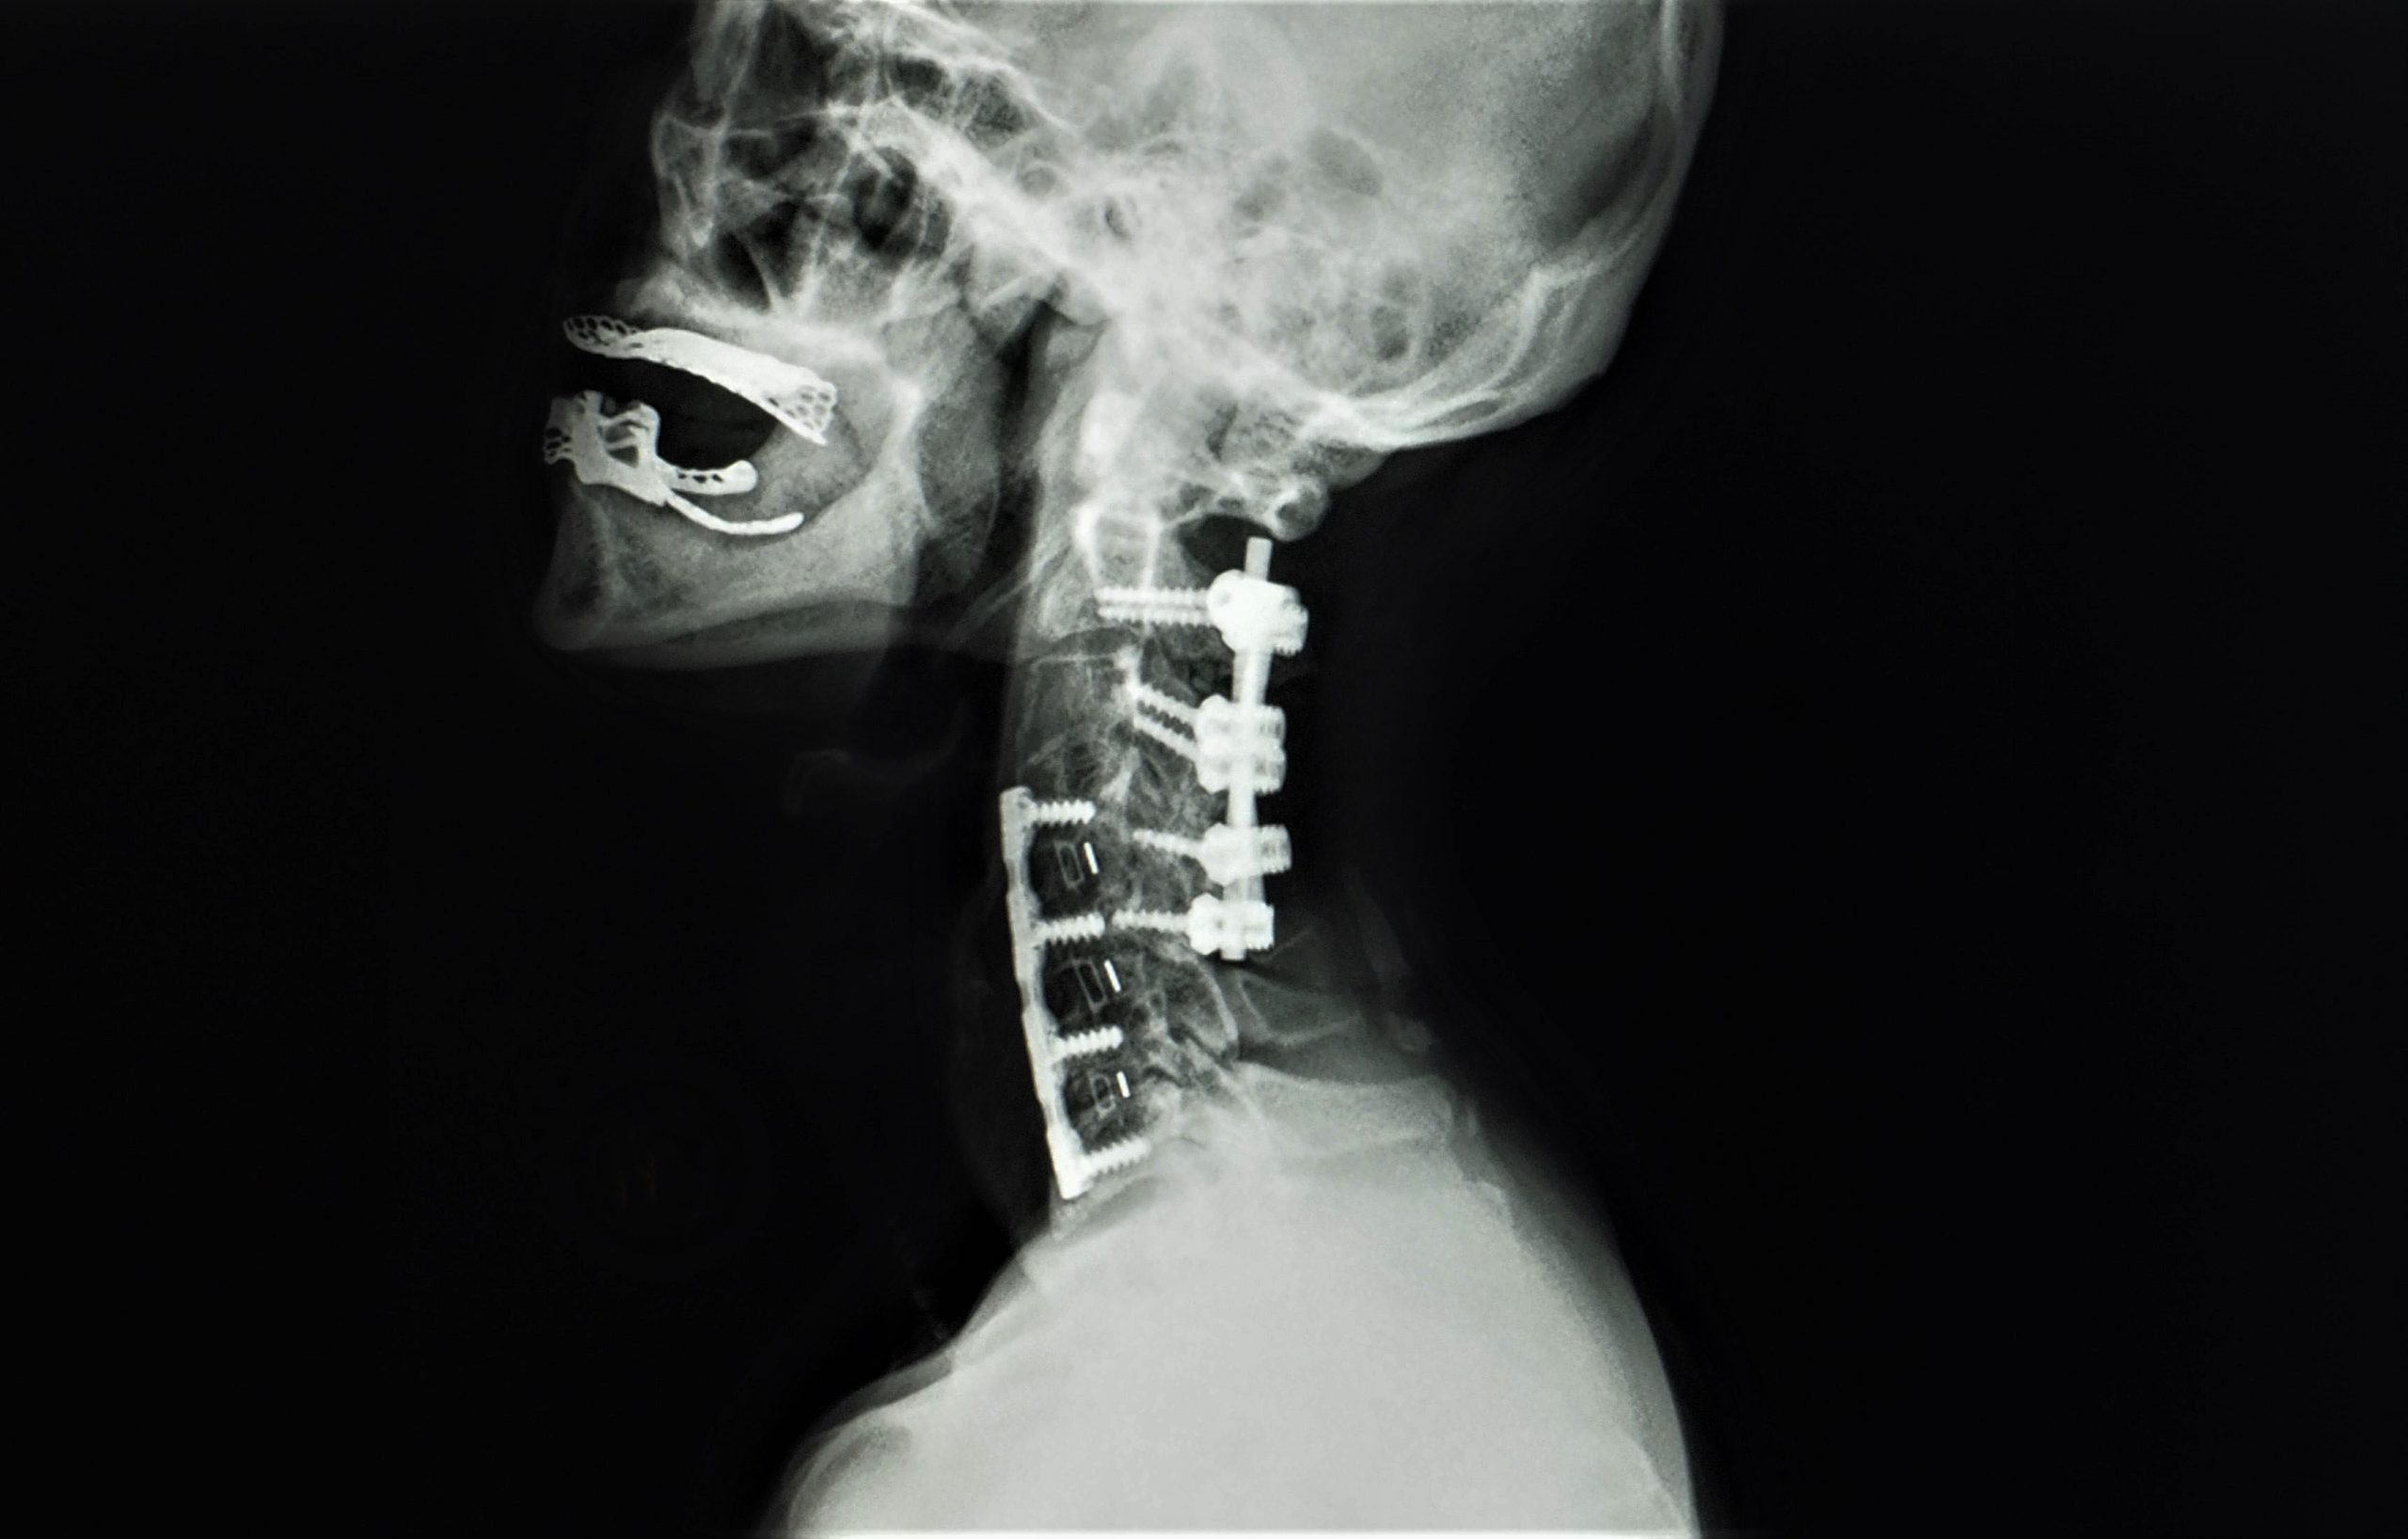

Learn about C-spine fusion, a surgical procedure designed to stabilize the cervical spine and alleviate chronic neck pain. This guide covers the recovery process, potential risks, and benefits of cervical spinal fusion, helping you understand how this intervention restores mobility and improves quality of life for patients dealing with degenerative disc disease or severe spinal instability.

TitleAnt. Cervical Discectomy & Fusion — Matthew Mian, MD